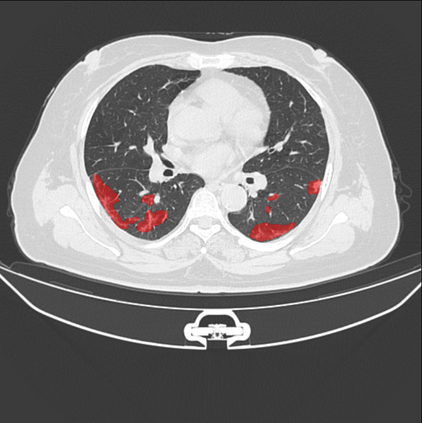

The COVID-19 pandemic has had a considerable impact on day-to-day life. Tackling the disease by providing the necessary resources to the affected is of paramount importance. However, estimation of the required resources is not a trivial task given the number of factors which determine the requirement. This issue can be addressed by predicting the probability that an infected patient requires Intensive Care Unit (ICU) support and the importance of each of the factors that influence it. Moreover, to assist the doctors in determining the patients at high risk of fatality, the probability of death is also calculated. For determining both the patient outcomes (ICU admission and death), a novel methodology is proposed by combining multi-modal features, extracted from Computed Tomography (CT) scans and Electronic Health Record (EHR) data. Deep learning models are leveraged to extract quantitative features from CT scans. These features combined with those directly read from the EHR database are fed into machine learning models to eventually output the probabilities of patient outcomes. This work demonstrates both the ability to apply a broad set of deep learning methods for general quantification of Chest CT scans and the ability to link these quantitative metrics to patient outcomes. The effectiveness of the proposed method is shown by testing it on an internally curated dataset, achieving a mean area under Receiver operating characteristic curve (AUC) of 0.77 on ICU admission prediction and a mean AUC of 0.73 on death prediction using the best performing classifiers.